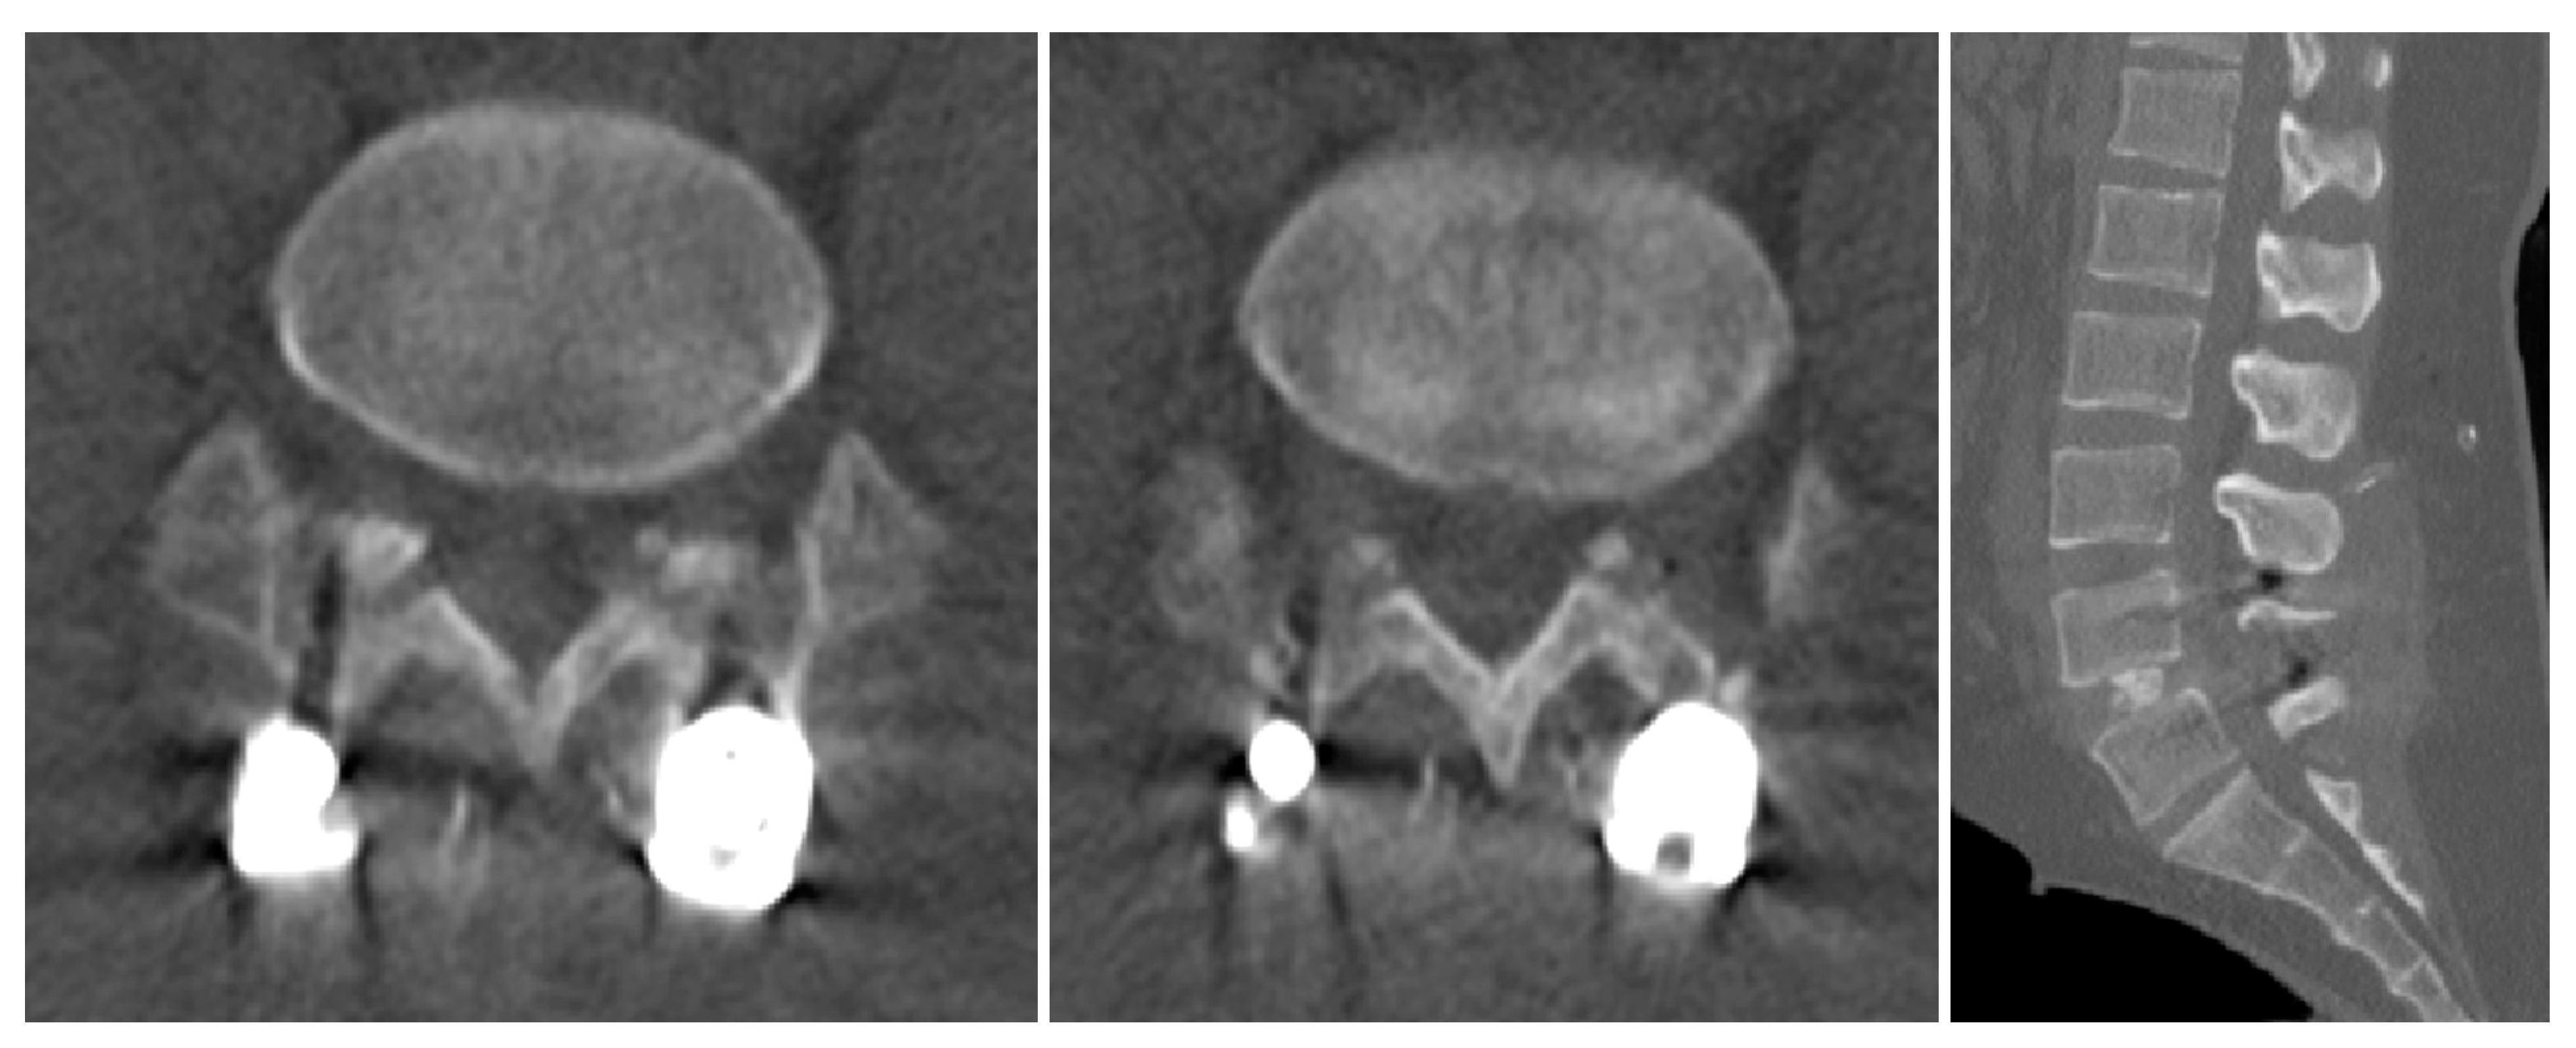

2.1. Case 1